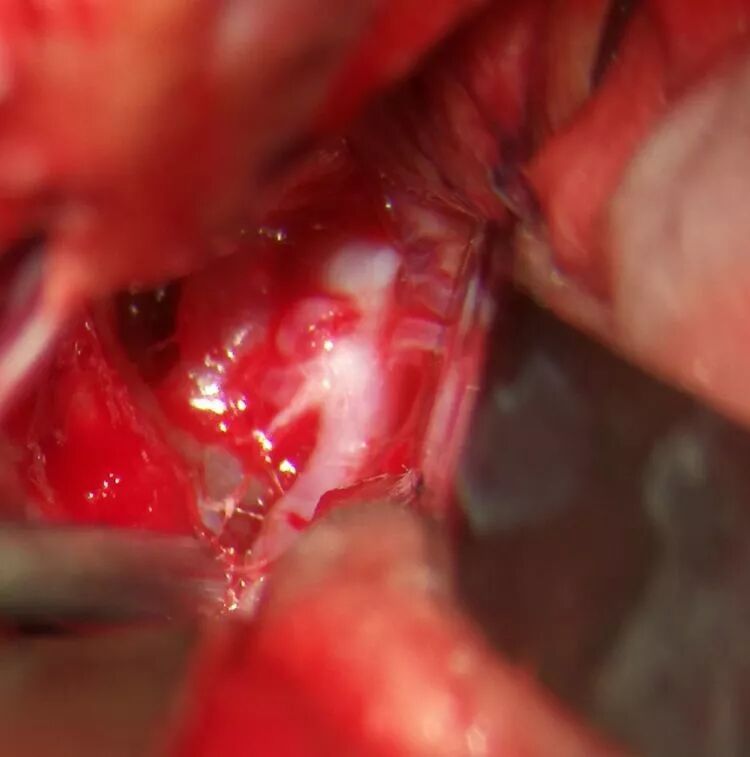

暴露颈内动脉、大脑前动脉A1以备临时阻断,脑板轻轻牵拉直回,解剖纵裂底部蛛网膜,轻松暴露同侧A2、前交通动脉、对侧A2、对侧A1及动脉瘤体,发现大动脉瘤位于前交通复合体背侧,瘤颈被同侧A1遮挡,瘤体被双侧A2和前交通动脉遮挡,前交通动脉前方又有一个小动脉瘤,同侧A2近端有4根穿支(包括返支)动脉,跨血管夹使用有困难,也担心前交通复合体丘脑穿支误夹,决定用长弯夹先夹闭可见动脉瘤颈,之后再以mini直角弯夹补充夹闭瘤颈,之后升血压过程中有异常出血,探查发现瘤颈依然有残留,在同侧A1外侧再补夹残留瘤颈,出血停止。前交通复合体前方小动脉瘤顺利夹闭。术中显微超声探查双侧A2血流回声正常,打开终板池,硬膜常规缝合。

3.在颅底外侧(前交通动脉复合体前下外侧)窥视前交通动脉复合体可以容易窥及其全貌(图1图2),当然需要轻拉直回,充分的暴露是准确夹闭的前提。